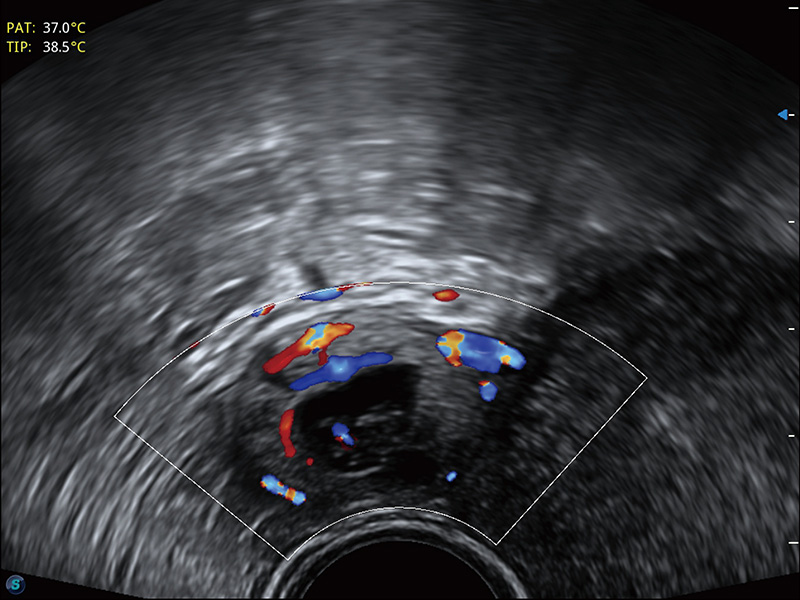

“生育问题”即关系民族复兴,也关系亿万家庭的幸福。随着婚育年龄推迟、社会压力增加等因素,越来越多人群也面临着“生不出、生不好”的问题。辅助生殖作为治疗不孕不育最有效的方法之一,也逐渐成为育儿新希望。而超声检查能为生殖需求人群的初诊评估提供宝贵的信息。 P20 Elite是狗万官方网站匠心打造的一款生殖应用型彩超。她继承狗万官方网站高端极光平台,突破性地将多款新型芯片及硬件模块进行整合,均衡了高端系统性能与小巧灵动机身。P20 Elite卓越的图像质量搭载专科探头,旨在为您提供全面的辅助生殖解决方案。

P20 Elite配备了丰富的生殖探头群和临床应用功能,在卵泡监测、穿刺取卵、胚胎移植、妊娠确认等领域,为生殖需求人群提供了新的临床机会,重新定义高端超声如何应用于生殖健康检查。